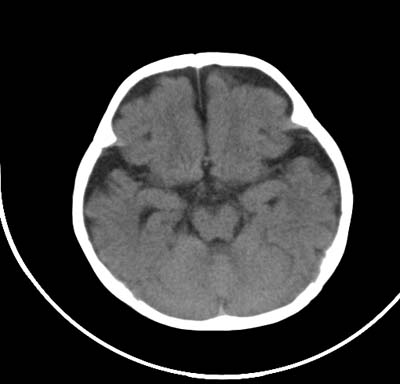

以下是引用影象小泰斗在2008-6-30 15:57:00的发言:[br]双侧额、颞部蛛网膜下腔增宽,纵裂加深, 支持外部性脑积水![br] 双侧基底节点状钙化!

以下是引用jiangjing在2008-6-30 17:19:00的发言:[br]双侧额、颞部蛛网膜下腔增宽,纵裂加深, 支持外部性脑积水![br] 双侧基底节点状钙化![宫内感染形成可能]